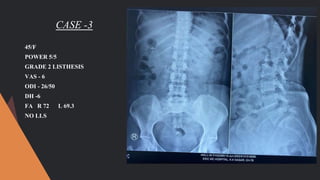

CASE -3

45/F

POWER 5/5

GRADE 2 LISTHESIS

VAS - 6

ODI - 26/50

DH -6

FA R 72 L 69.3

NO LLS